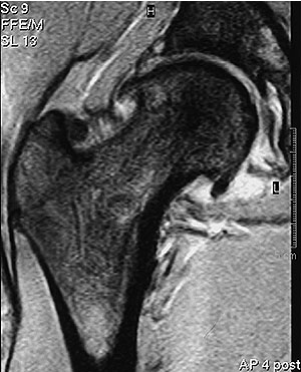

Nicht selten bedingt die Coxarthrose aufgrund der starken Schmerzen das Einsetzen eines künstlichen Hüftgelenkes. Degenerative Veränderungen am Hüftgelenk sind bei 17% der Männer und 10% der Frauen über 55 im Röntgenbild sichtbar. In etwa zwei Dritteln der Fälle handelt es sich dabei um eine Sekundärarthrose aufgrund einer vorbestehenden Deformität. Diese kann angeboren oder entwicklungs- respektive unfallbedingt sein. Auch Entzündungen und Infektionen können als Ursache dazu führen. In einem Drittel der Fälle ist die auslösende Ursache nicht ersichtlich. Die Bemühungen der Orthopädie zielen dahin, möglichst früh, also vor dem eigentlichen Entstehen degenerativer Gelenkabnützungen, den natürlichen Krankheitsverlauf positiv zu beeinflussen. Mit gelenkerhaltenden operativen Massnahmen soll die Implantation eines künstlichen Hüftgelenks möglichst lange hinausgezögert werden. Denn das Einsetzen einer Gelenkprothese birgt das Risiko von Komplikationen (Prothesenlockerung, Infekt, Ausrenkung), die operative Folgeeingriffe (Prothesenwechsel, -ausbau) zur Folge haben können. Zudem beträgt das durchschnittliche Überleben eines künstlichen Hüftgelenks rund 15 Jahre. Aus diesem Grund darf die Indikation für das Einsetzen eines künstlichen Hüftgelenks nicht leichtfertig gestellt werden, insbesondere nicht bei Patienten unter 60 Jahren. Nicht selten sind junge, sportlich aktive Patienten unter 30 Jahren oder Berufstätige mit schwerer körperlicher Arbeit von diesen einschränkenden Leisten- und Hüftbeschwerden betroffen. In der Vergangenheit dürften derartige eschwerden gerade bei Sportlern über Jahre als Adduktorenzerrung behandelt worden sein. Wahrscheinlich beschleunigt die Kombination von nicht optimalen anatomischen Voraussetzungen am Hüftgelenk und die vermehrte körperliche Belastung durch Sport oder Beruf die krankhaften Veränderungen. Insbesondere bei jungen Patienten, bei denen knöcherne Reaktionen noch nicht erkennbar sind, erweist sich die Magnetresonanztomographie (MRI) bei der Diagnosestellung als sehr hilfreich (Abb. 3).

Einrisse an der knorpligen Gelenklippe am Pfannenrand sowie Abnützungen des daran anschliessenden Gelenkknorpels können erkannt werden.